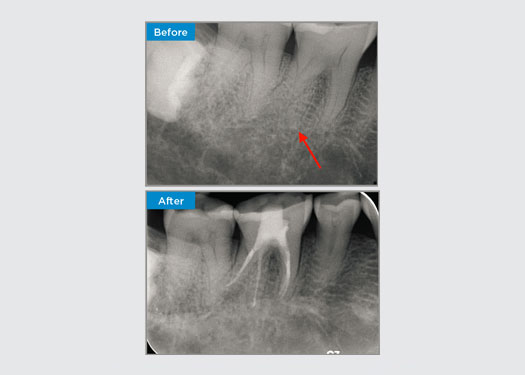

Eine 35-jährige Patientin stellte sich nach Überweisung durch einen spezialisierten Parodontologen vor. Bei der ersten endodontischen Untersuchung erwähnte die Patientin, dass vor dem Einsetzen der Krone an Zahn 16 zwei Jahre zuvor eine Kronenverlängerung durchgeführt worden war. Zwei Monate zuvor hatte die Patientin eine Schwellung der palatinalen Gingiva festgestellt. Der Hauszahnarzt der Patientin hatte eine 7 mm große parodontale Tasche angrenzend an den palatinalen Sinustrakt in Verbindung mit Zahn 16 entdeckt. Die Patientin wurde an einen spezialisierten Parodontologen überwiesen. Der spezialisierte Parodontologe diagnostizierte eine primäre endodontische – sekundäre parodontale Läsion. Die Mundhygiene der Patientin war zufriedenstellend, und sie ging regelmäßig zum Zahnarzt. Zahn 16 war perkussionsempfindlich. Es wurde festgestellt, dass die Kronenränder zufriedenstellend waren und die parodontalen Taschen um Zahn 16 herum auf der bukkalen Seite weniger als 2 mm tief waren, aber auf der palatinalen Oberfläche, angrenzend an den Sinustrakt, war eine 6,5 mm tiefe isolierte parodontale Tasche vorhanden. Die thermische Untersuchung von Zahn 16 ergab eine negative Reaktion. Zahn 16 wies Risikofaktoren für eine apikale Parodontitis auf, wie z. B. eine negative Reaktion auf eine thermische Untersuchung, Perkussionsempfindlichkeit, eine Vorgeschichte mit einer tiefen Restauration nach einer Kronenverlängerung und eine röntgenologisch erkennbare periapikale Erkrankung. Bei Zahn 16 traten in der Vergangenheit keine Schmerzen beim Kauen oder Abbeißen auf, was auf einen Riss hinweisen könnte, der mit der Pulpa und/oder dem parodontalen Gewebe kommuniziert. Die Patientin wies keine Risikofaktoren für eine Parodontalerkrankung auf, und es lagen keine abnorm tiefen Taschen an anderen Zähnen vor.

Dr. Omar Ikram, Endodontist, Crows Nest, NSW Australien